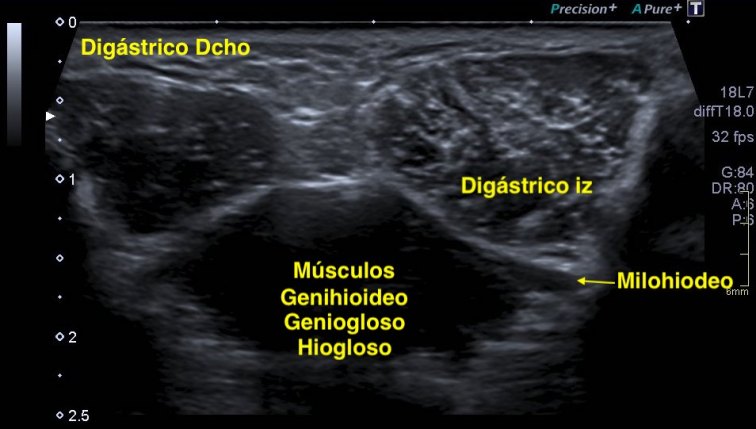

Si colocas la sonda en el mentón, en axial vas a encontrar este músculo Digástrico, que se verá muy bien, superficial, en un plano intermedio tendrás el músculo Milohiodeo y en la profundidad los músculos Geniohideos, Geniogloso y el Hiogloso…Mira:

El Músculo Milohioideo se encuentra en un plano medio, es fino y separa el plano superficial muscular, del profundo, en la imagen superior ves una pequeña porción de este músculo. En el plano profundo un grupo de varios músculos, que he mencionado más arriba y que son músculos extrínsecos de la lengua, situados en la región más medial de esta localización submentoniana estudiada.